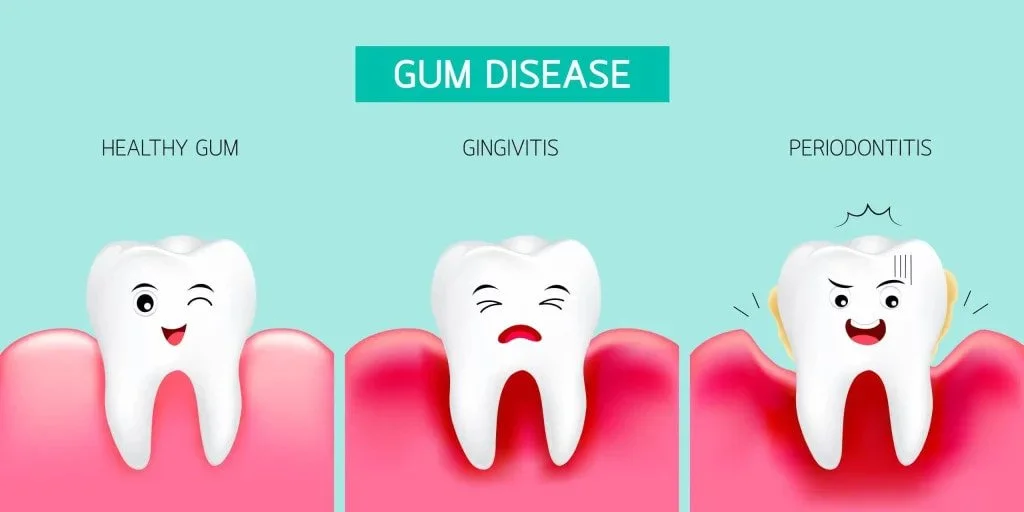

When gums bleed during brushing, the soft gum tissue is inflamed and irritated. Healthy gums are firm, pink, and do not bleed even with regular brushing.

Gingivitis is the leading cause of bleeding gums worldwide. It is the early stage of gum disease caused by plaque buildup along the gum line.

When plaque — a sticky film of bacteria — is not properly removed, it irritates the gum tissue. This leads to redness, swelling, and tenderness.

When gingivitis is left untreated, it progresses to periodontitis. This is a serious and more destructive form of gum disease.

Periodontitis damages the connective tissue and bone that hold teeth in place. Symptoms include deep gum pockets, gum recession, and loose teeth.